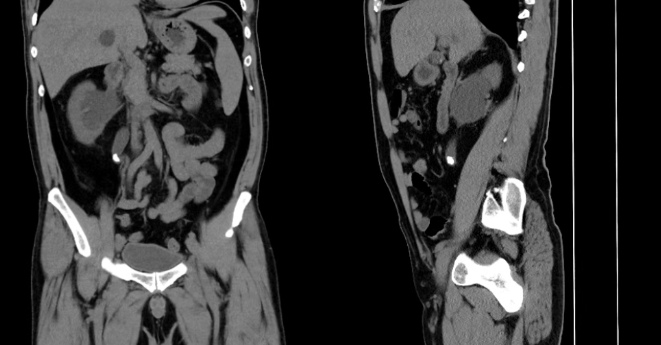

入院完善全腹CT檢查提示:右側(cè)輸尿管上段結(jié)石位置無變化、右腎積水較前明顯加重,影像學(xué)提示:輸尿管走行迂曲、管腔狹窄,結(jié)石已長期嵌頓、包裹與管壁粘連緊密,屬于復(fù)雜性輸尿管結(jié)石,常規(guī)碎石難度大、風(fēng)險(xiǎn)高,極易出現(xiàn)結(jié)石漂移、輸尿管損傷。